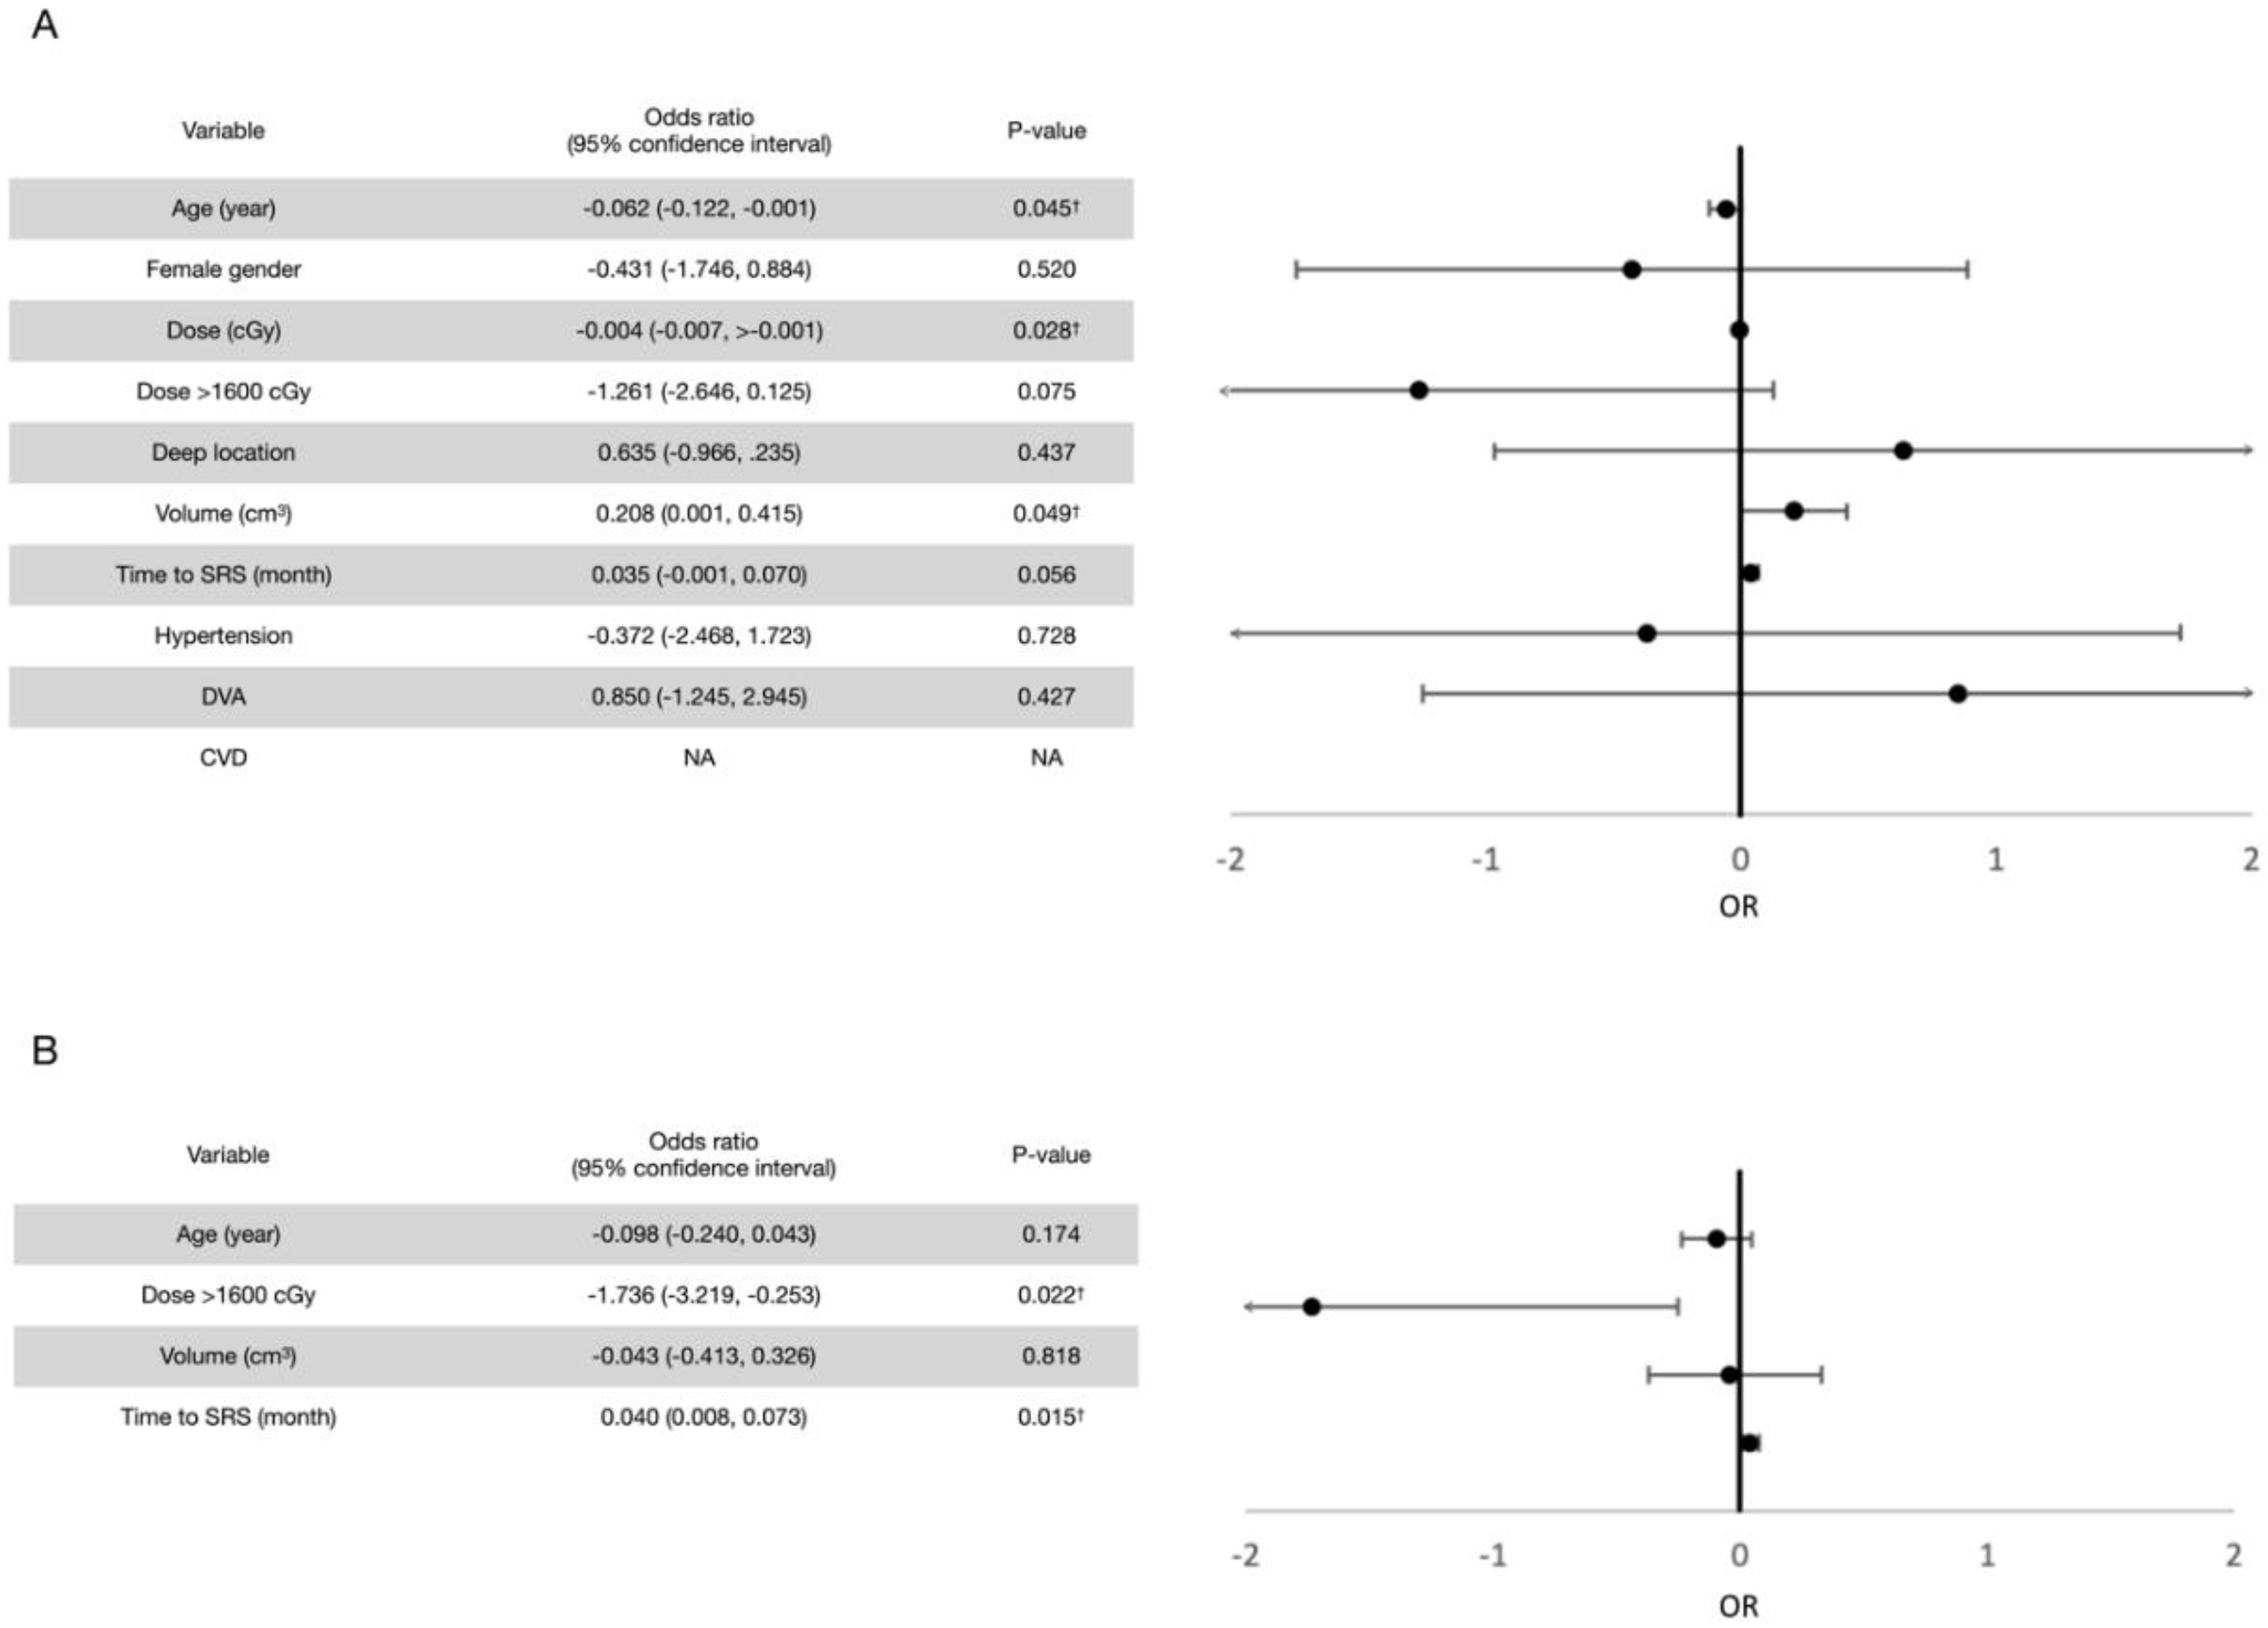

3.2. Post-Radiosurgical Rebleeding Analysis

3.4. Post-Radiosurgical Perifocal Brain Edema